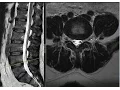

análise anatômica dos cortes axiais esta linha corresponde ao nível do corte então estamos cortando aqui na altura do corpo vertebral então aqui temos o corpo vertebral músculo pessoas músculo pessoas músculo quadrado lombar a musculatura para espinhal corpo vertebral canal vertebral canal raquidiano essas estruturas que parecem vários pontos são as raízes da Calde equina cortadas transversalmente e aqui temos a duram Mater e aqui aqui temos os forames intervertebrais aqui já estamos no nível do disco intervertebral Então temos o anel fibroso anel fibroso ele é redondo aqui a superfície posterior é convexa é côncava aliás é côncava

faz essa curva aqui para dentro dele é côncava ela pode ser retificada no nível de L4 L5 E ela pode ser retificada ou discretamente convexa no nível L5 bar S1 isso é normal mas do nível L4 para cima ela é sempre com esse formato côncava e aqui a parte central o núcleo pupos que é mais branco porque tem mais água quanto mais água mais branco na sequência ponderada em T2 e aqui a gente vê as raízes da Calde Quina ada transversalmente aqui a duram Mater e aqui gordura no espaço epidural aqui os processos articulares processos

articulares aqui e articulação interapofisária articulação interapofisária o que tá brilhando aqui é cartilagem da articulação interapofisária e aqui a gordura epidural e aqui ligamento Amarelo processo espinhoso e lâminas e oos forames intervertebrais com as raízes saindo aqui Aqui estamos no nível de um corpo vertebral canal vertebral pedículos pedículos processos articulares lâminas processo espinhoso gordura epidural epidural posterior duramáter e raízes da Calde quí e líquor aqui forames intervertebrais as raízes saindo e esse aqui são pequenos vasos radiculares o canal raquidiano as raízes da Calde Quina a duram Mater gordura epidural aqui a gente vê melhor o

ligamento Amarelo essa faixa escura ligamento amarelo de um lado e do outro gordura epidural duram Mater as raízes da Calde equina as raízes saindo aqui né os gangos das raízes saindo aqui pelo forame intervertebral anel fibroso núcleo pulposo articulação interapofisária processo articular processo articular lâminas processo espinhoso e aqui a musculatura par espinal aqui o tecido subcutâneo músculo pessoas de um lado pessoas do outro ali a bifurcação da horta nas ilíacas e aqui a veia cava inferior e assim vai sempre a mesma coisa veja os forames veja as raízes saindo as raízes da Calde Quina o

canal raquidiano duramáter espa epidural lâminas processo espinhoso veja que os cortes são feitos Paralelos ao eixo do disco intervertebral pra gente ter a imagem do disco aqui as raízes saindo pelos forames né raiz saindo aqui e as raízes da Calde equina que ficam aqui dentro processos articulares articulação interapofisária lâminas processos espinhoso e aqui já o sacro canal vertebral sacral e as raízes aqui saindo pelo Canal eh pelos fonos sacr vai sair pelos fâ sacris mais abaixo Então essas são as principais estruturas que nós vemos no axial na sequência ponderada em T2 então nós vimos as